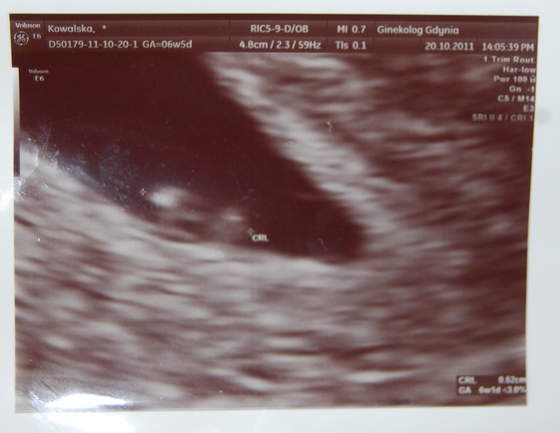

śliczne malenstwo ahh :*